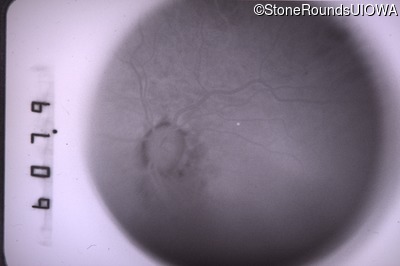

Infrared Fundus Photograph - Right - 20/40 +2

Exemplar